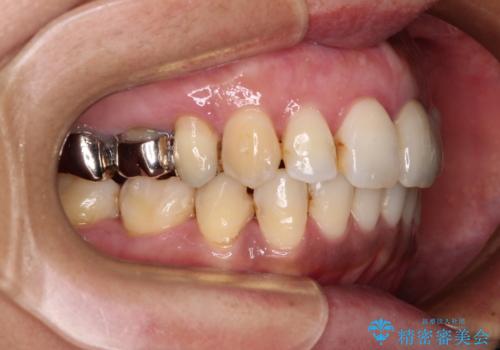

口元を引っ込めることができたため、口を閉じるときに力が入っていて皺のよっていた顎先も、スムーズに閉じられるようになったことで力がかからなくなりました。

変色して気になっていた前歯も、オールセラミッククラウンで自然な色合いにすることができました。